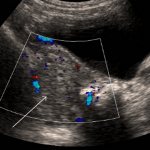

- electroencephalography;

- CT scan;

- Magnetic resonance imaging;

- X-ray examination of the skull;

- ECG study (to exclude the cardiogenic origin of seizures).